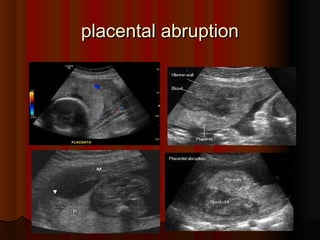

placental abruption

Crescent of

Crescent of avascular

avascular

low echogenicity

between placenta and

uterine wall consistent

with

with placental

placental

abruption

abruption.

placental abruption placental abruption . . Crescent of Crescent ofavascular avascular low echogenicity low echogenicity between placenta and between placenta and uterine wall consistent uterine wall consistent with with placental placental abruption abruption. .